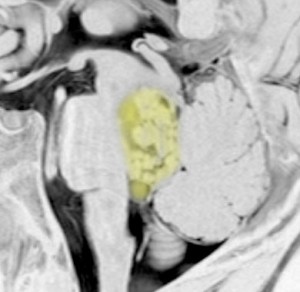

第4脳室とは

後頭部に近い所にあります。黄色が第4脳室で,髄液の通り道(出口)です。

前方には脳幹部,後ろは小脳虫部です 。

上は細い中脳水道につながって,下はマジャンディー孔と左右のルシュカ孔に開いています。